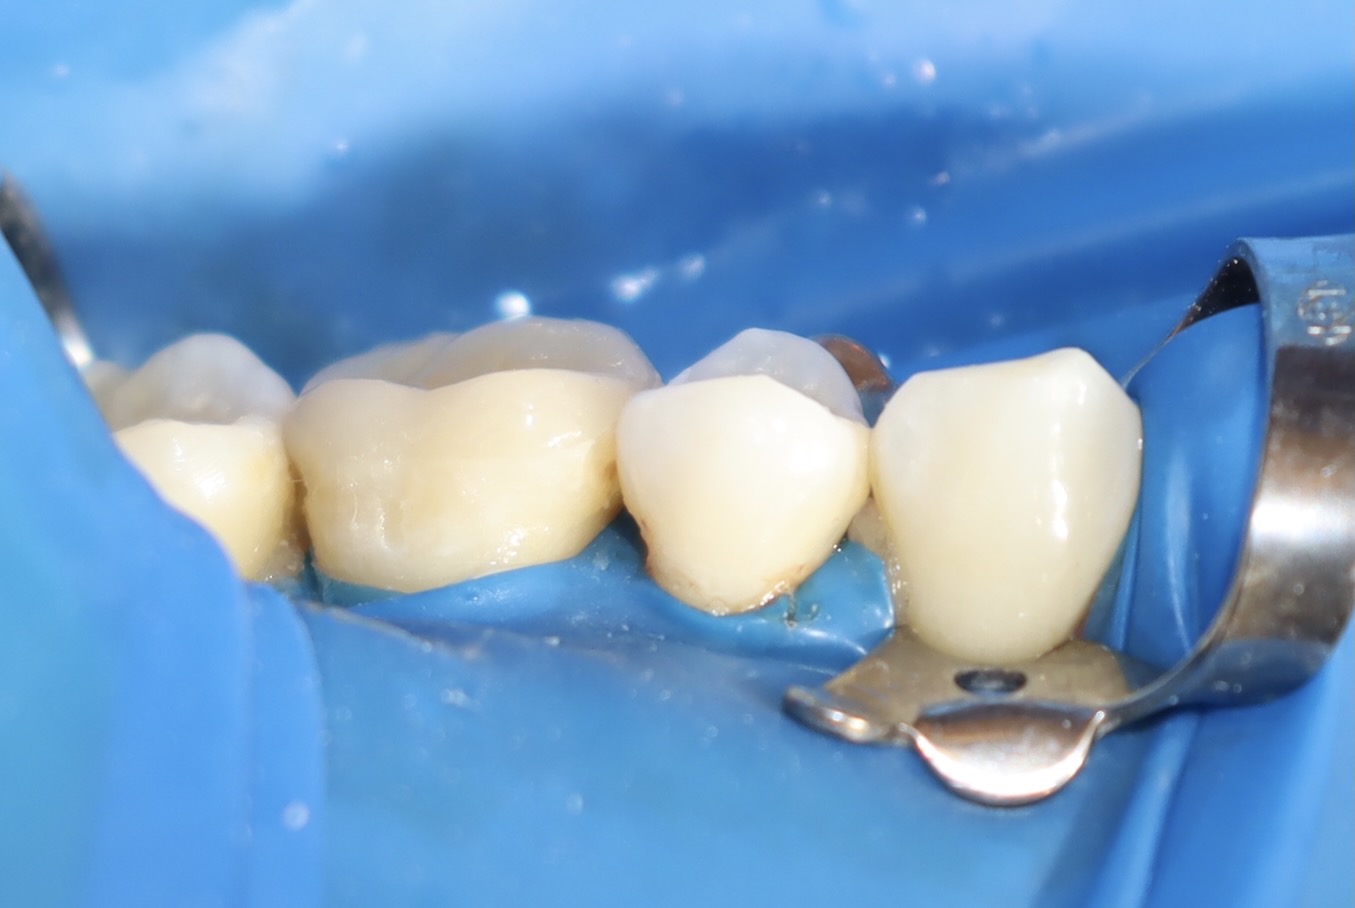

術後照片

術中照片